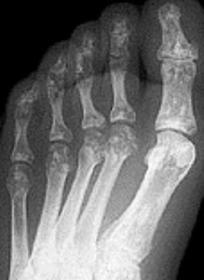

What disease is this? | Rheumatoid arthritis |

What disease is this? What do the arrows indicate? | Gout Arrows = 'punched out' erosions |